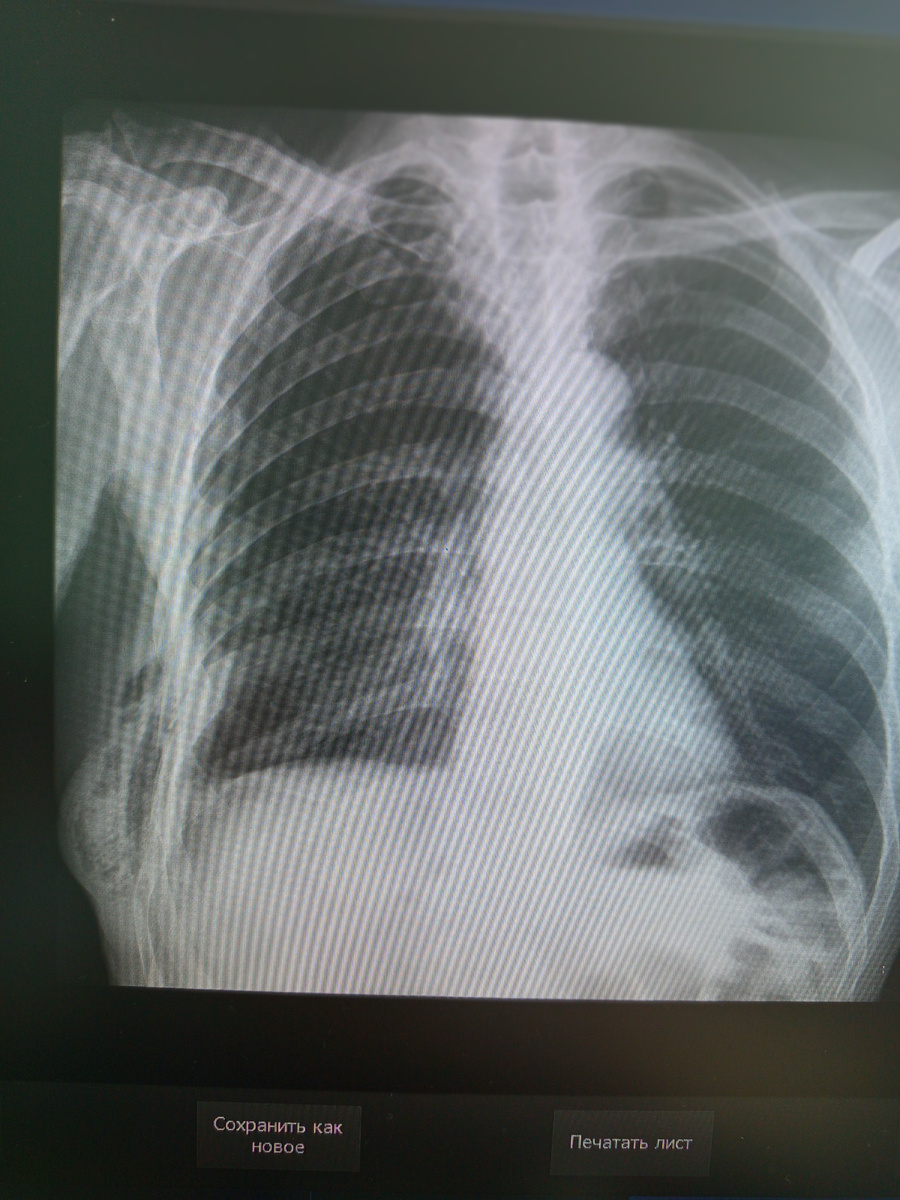

Вот и завезли такую пациентку , из области , 23 года , автодорожка . Она , ее младшая сестра , их мама , наняв машину , ехали отдыхать на какую-то базу.

Мать погибла до приезда медиков , водитель остался в районе в тяжёлом состоянии , сестру к нам привезли еще в субботу , как более пострадавшую , а женщину перевели сегодня. И назначили:череп , легкие , таз, поясничный отдел(в двух проекциях) и плечо.

С большой аккуратностью по причине точного перелома плеча переложили ее на стол.

Начать решаю с плеча.

И разумеется речь о второй проекции, боковой, сразу отпадает.Не ляжет она на бок , даже пробовать не буду , она и так с трудом переносит боль. В дополнительной информации так и указали , что нет технической возможности.